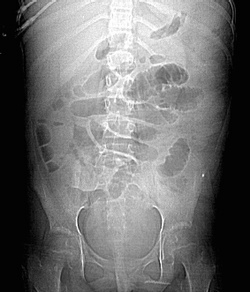

RADIOLOGY: GASTROINTESTINAL: GI: Case# 32789: GRAFT VS HOST DZ - GB EDEMA & STONE. Eleven year old female with allergenic bone marrow transplant.Now with elevated temperature, sepsis, and hypertension. 1) Thickening of the small bowel with mild dilatation. This may be secondary to patients known diagnosis of graft versus host disease. Other etiologies which may cause submucosal edema including infection is also possible. 2) No intraabdominal abscess. 3) Poor corticomedullary differentiation consistent with renal dysfunction. 4) Hepatomegaly, gallbladder sludge with no intrahepatic biliary dilatation.